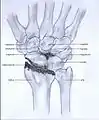

Post-traumatic osteoarthritis can be classified into four stages.[1][7] These stages are similar between SLAC and SNAC wrists. Each stage has a different treatment.

- Stage I: the osteoarthritis is only localized in the distal scaphoid and radial styloid.

- Stage II: the osteoarthritis is localized in the entire radioscaphoid joint.

Stage I

Stage II